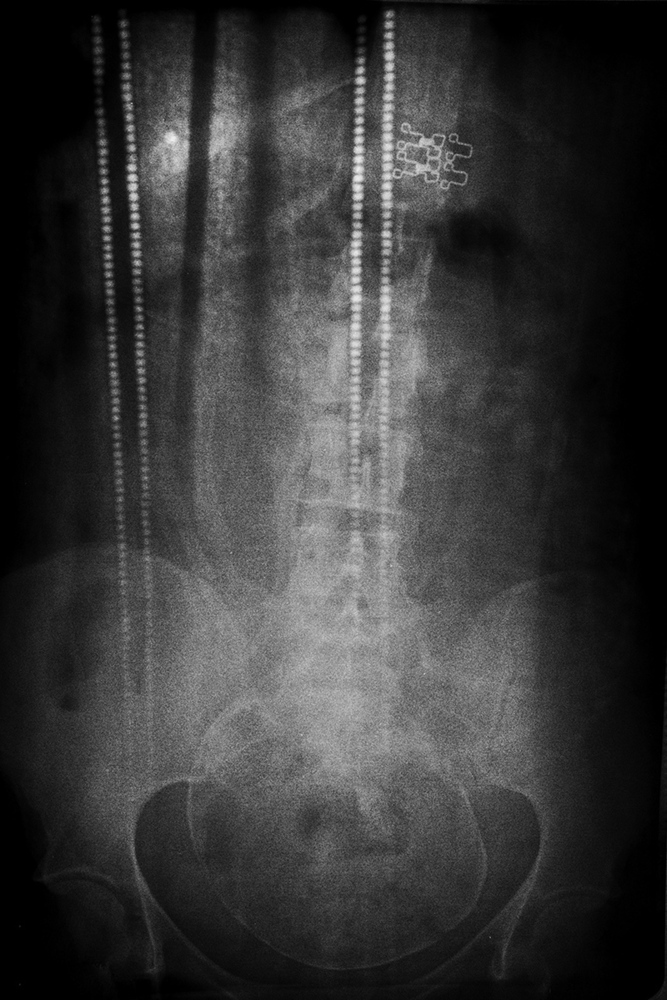

© Tuane Eggers, Symbiogenesis, Porto Alegre/RS, Brazi